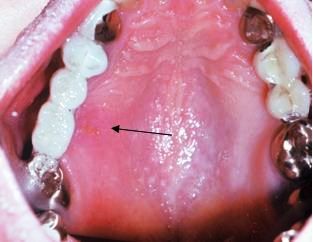

In this patient with secondary HSV infection caused by latent herpesvirus, the recurrent lesion appears on the attached gingival tissue adjacent to the teeth, including the palate. Secondary infection may last 10 to 14 days and reoccurs in response to stress, fever, trauma, and hormonal alterations.

Photo courtesy of Dr Jeff Burgess